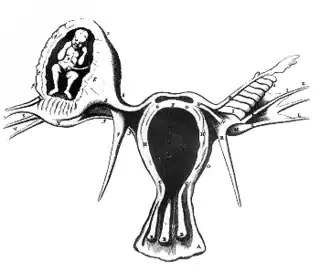

![]() Ectópico, ilustración de Regnier de Graaf | ||

Un embarazo ectópico (del gr. ἐκ, "fuera", y τόπος, "lugar") es una complicación del embarazo en la que el óvulo fertilizado o blastocito se desarrolla en los tejidos distintos de la pared uterina,[2] ya sea en la trompa de Falopio (lo más frecuente), en el ovario, en el canal cervical, en la cavidad pélvica o en la abdominal. Cuando el embarazo ocurre en el endometrio del útero se le conoce como embarazo eutópico.[3] El embarazo ectópico se produce por un trastorno en la fisiología de la reproducción humana que lleva a la muerte fetal,[4][5] y es la principal causa de morbilidad fetal y materna en el primer trimestre con 2 o 3 semanas del embarazo.[6]

Cuando ocurren, los embarazos ectópicos suelen desarrollarse en una de las trompas de Falopio (embarazo tubárico). Son infrecuentes los embarazos en el canal cervical, en el ovario o en la cavidad abdominal o pélvica. Un embarazo ectópico constituye un riesgo para la vida, por lo que debe ser interrumpido lo antes posible. Según algunas estadísticas, 1 de cada 826 mujeres con embarazos ectópicos muere por complicaciones. En España se estima que el embarazo ectópico constituye aproximadamente el 2,3 por ciento del número total de embarazos.[3]